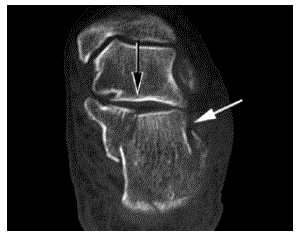

Considere a figura abaixo como sendo uma tomografia computadorizada do calcâneo, onde a seta preta mostra uma fratura articular e a seta branca mostra uma fratura extra-articular.

A fratura mostrada é classificada, segundo SANDERS, como sendo do tipo